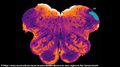

في 23 نوفمبر 2018 أعلن العلماء عن اكتشاف منطقة مختبئة Endorestiform Nucleus في المخ، يمتاز بها البشر، وقد تساعد في علاج مرض پاركنسون ومرض العصبون الحركي. عثر الأستاذ جورج پاكسينوس من مركز أستراليا للعلوم العصبية هذه المنطقة المختبئة، والمسماة Endorestiform Nucleus، وحسب قوله فإن: هذه "المنطقة مثيرة للاهتمام لأنها تبدو غير موجودة في المكاك الريسوسي والحيوانات الأخرى التي درسناها". تقع هذه المنطقة بالقرب من التقاء الحبل الشوكي بالمخ، ويقتصر وجودها على المخ البشري. تجمع هذه المنطقة بين المعلومات الحسية والحركية لتحسين وضعية الجسم، والتوازن، والحركات الدقيقة. وعلى الرغم من عدم المعرفة الدقيقة لوظيفة هذه المنطقة إلا أنه بالنظر إلى الجزء الذي تقع فيه داخل الدماغ، فمن المرجح أنها تلعب دوراً رئيسياً في التحكم الحركي الدقيق. [5]

موقع المنطقة المختبئة في المخ.